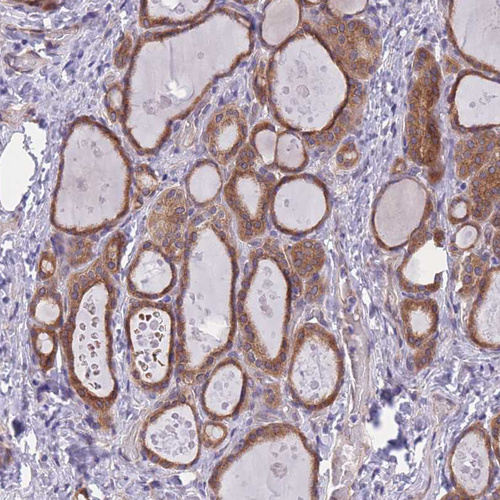

Immunohistochemical staining of human thyroid gland shows strong cytoplasmic positivity in glandular cells.